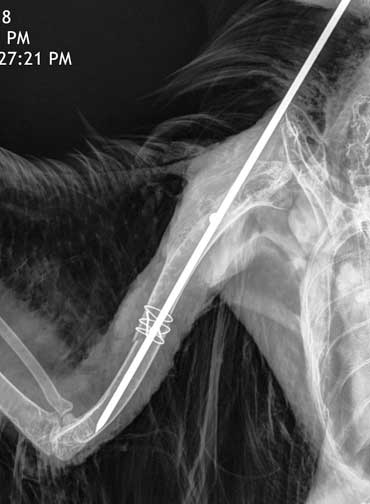

What the pin looks like in a hawk from our Wildlife Program with a fractured humerus. The wire that is giving additional support is called a cerclage wire. It also needs to be sterile, since it stays in this bird forever. The pin was taken out a few months later. You can see the whole story of this hawk, from beginning to end, including the surgery and release.

To give you a preview of this story, here he is at the rehabber convalescing